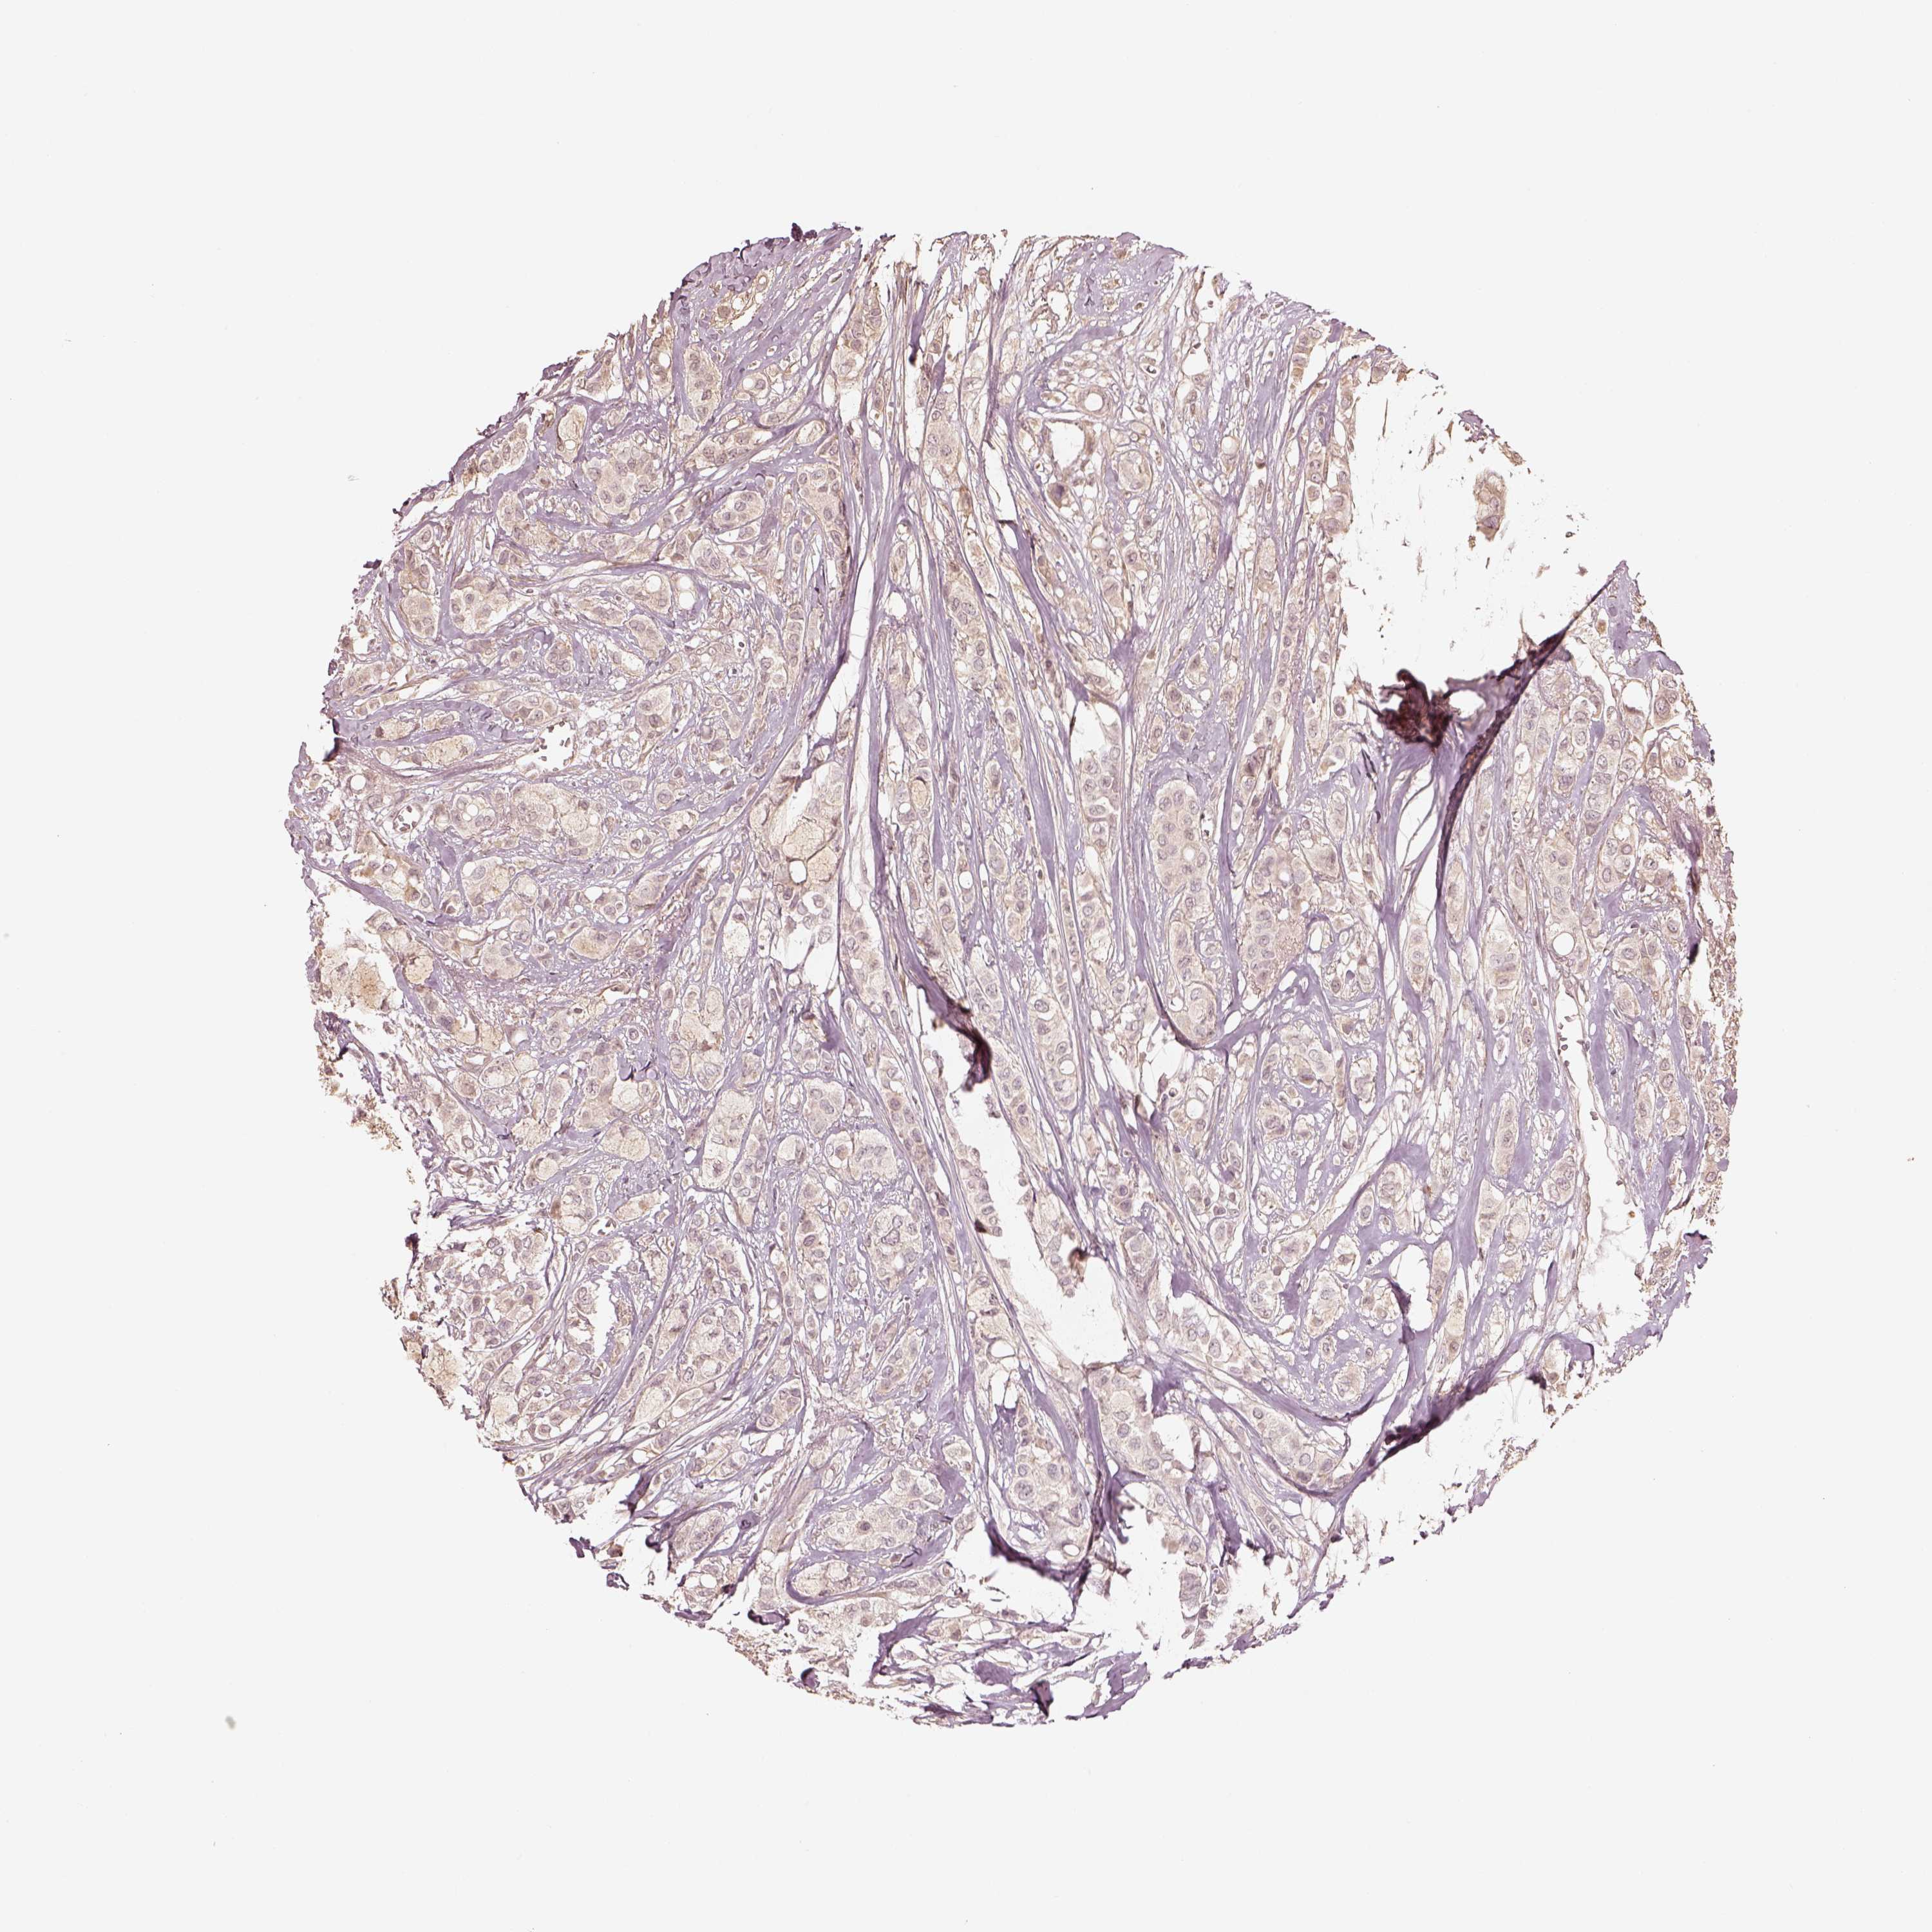

CANCER BREAST CANCER Show tissue menu

BRCA TCGA BRCA VALIDATION PROTEIN EXPRESSION